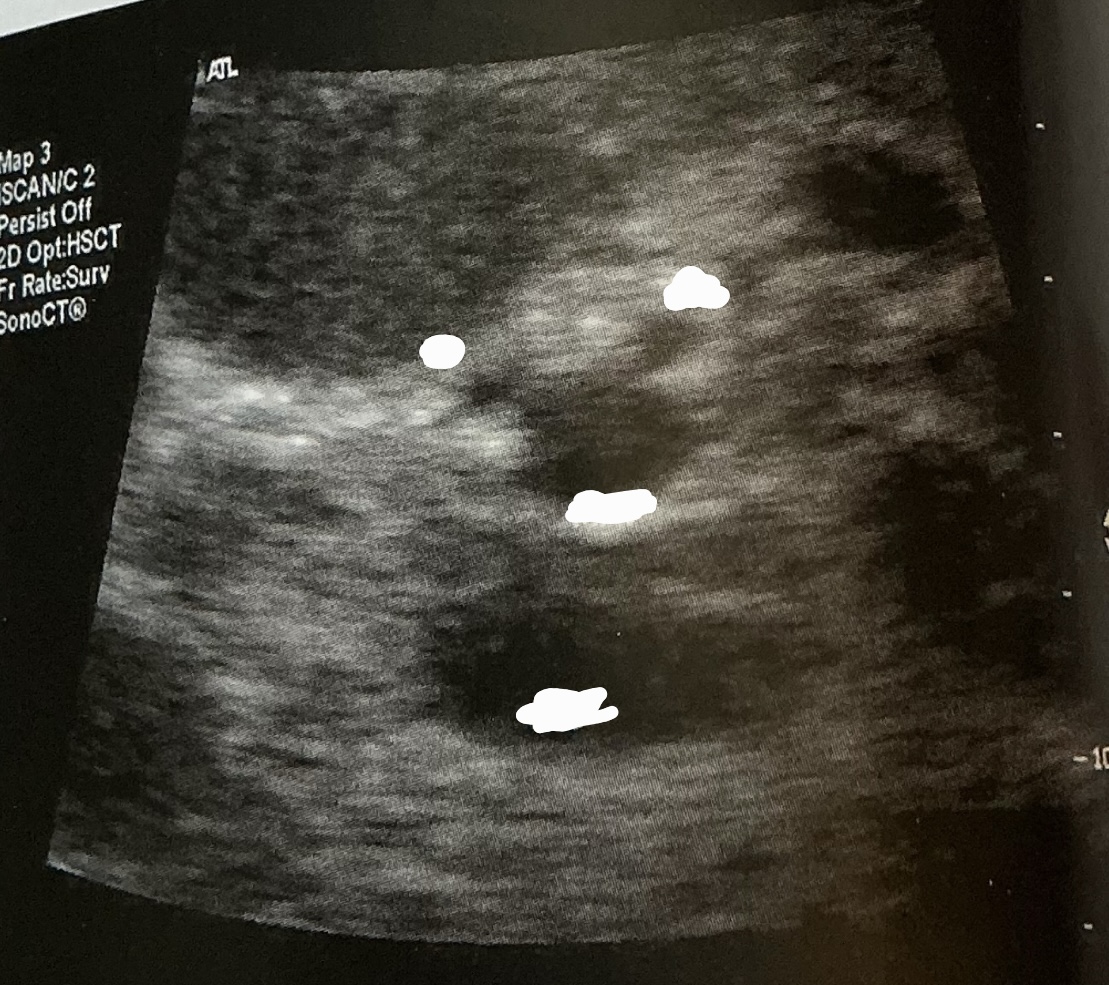

What is this photo depicting?

situs inversus